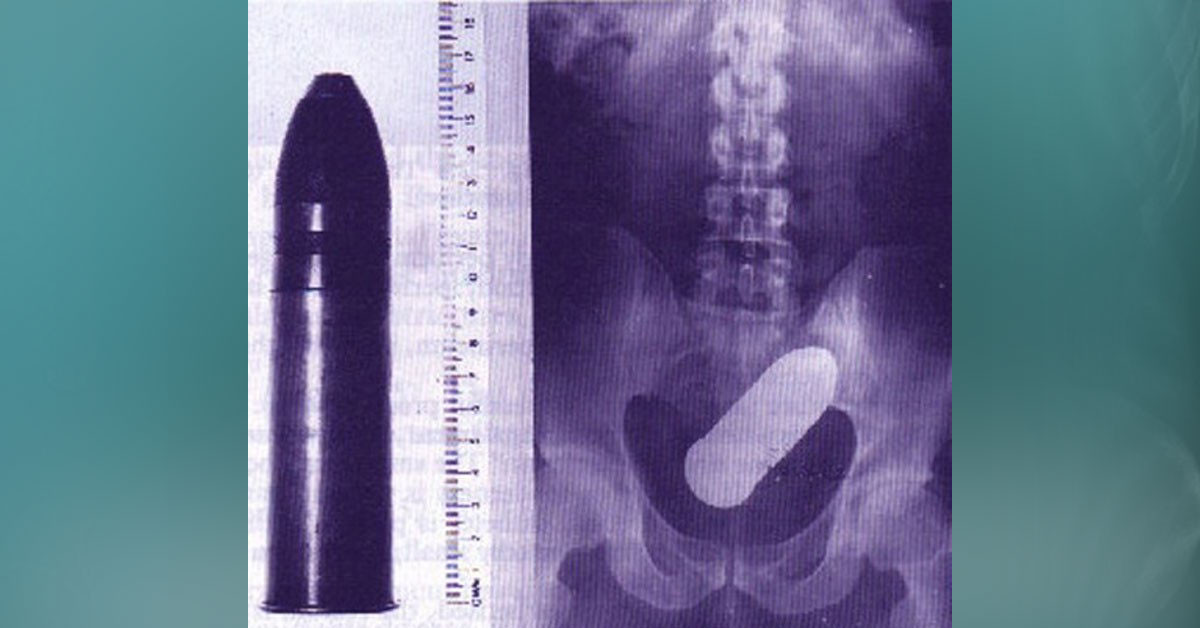

ABD'de bir kadın odası partneri ile eğlenceyi ararken yaptıkları yanlış bir hareket yüzünden hemen taşıdılar. Bu da her türlü seks oyunlarının sonu hastanelik olan insanlara akıllara geitrdi.

Sevgilisi ile yaramazlık yapmak isteyen kadın ve erkek arkadşası yapmak daha eğlenceli bir yatak hayatları olsun diye asla yapmamaları gereken bir şey yaptı. Saatler ilerledikçe büyük bir acı hisseden kadın en sonunda dayanamadı ve utana sıkıla koştu. Bu da akıllara seks kazalarını dile getirdi.